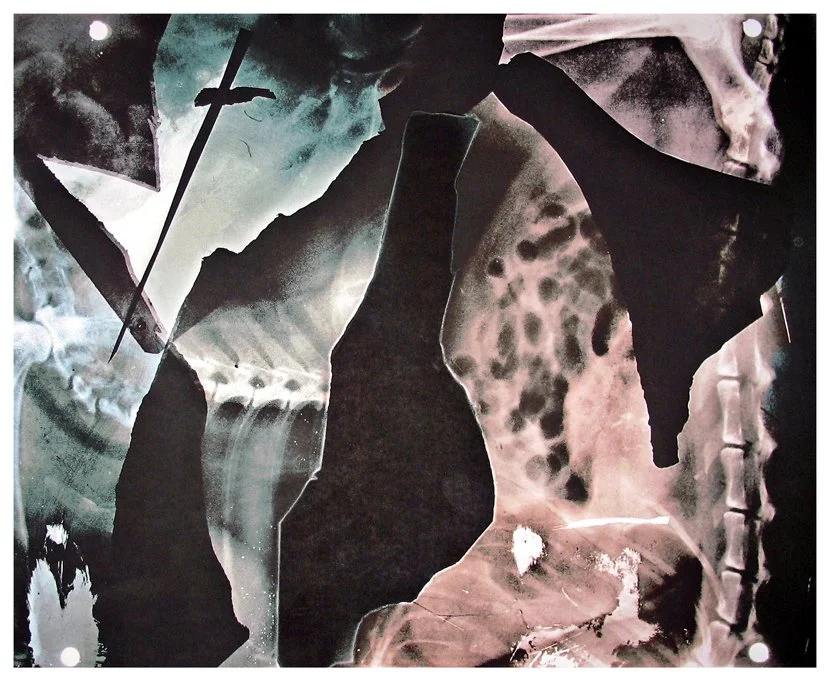

Insight is a series of collaged X-ray fragments, which were digitally composed into giclée prints. They speak not only of the body’s interior, but of the human experience it contains.

Drawn from DNA sequencing gels, mammograms, ultrasound scans, and cell cultures grown in Petri dishes, these compositions reframe diagnostic materials as metaphoric landscapes. What once served to identify illness becomes a language of line, texture, and light. They serve as a quiet meditation on fragility, resilience, and the unseen forces that shape us.

Each image in Insight is both an anatomical artifact and an artistic inquiry. Each one is part of my ongoing exploration of the relationship between Art, Science, and Medicine. Through digital layering and compositional play, I aim to dissolve the boundary between clinical detachment and emotional intimacy by inviting viewers to look inward and find meaning in the microscopic.

Sword 9.75" x 9" x 4.75"